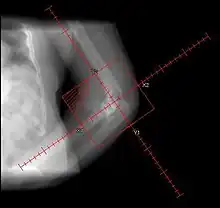

Prophylactic radiation therapy for the prevention of heterotopic ossification has been employed since the 1970s. A variety of doses and techniques have been used. Generally, radiation therapy should be delivered as close as practical to the time of surgery. A dose of 7-8 Gray in a single fraction within 24–48 hours of surgery has been used successfully. Treatment volumes include the peri-articular region, and can be used for hip, knee, elbow, shoulder, jaw or in patients after spinal cord trauma.